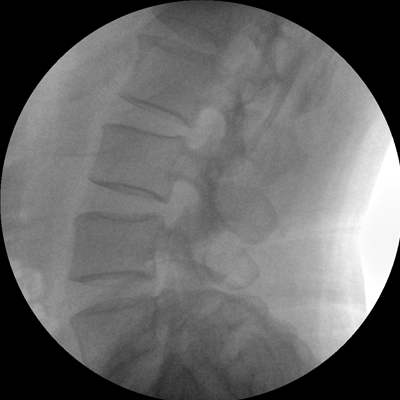

專業(yè)的圖像處理系統(tǒng),為您提供高分辨率、高灰階圖像。